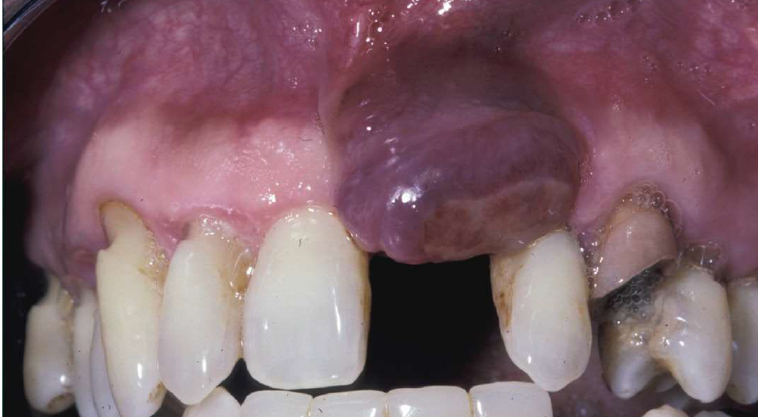

peripheral giant cell granuloma

relatively common reactive lesion of the gingiva

histologically identical to the central giant cell granuloma

bluish-purple lesion

radiographic- may cause “cupping” resorption (saucerization)

almost exclusively on the gingiva or edentulous alveolar ridge

peripheral giant cell granuloma histopathologic features

chocolate chip cookie like histology

peripheral giant cell granuloma treatment and prognosis

local excision down to the underlying bone

removal of local factors

approximately 10% recurrence rate